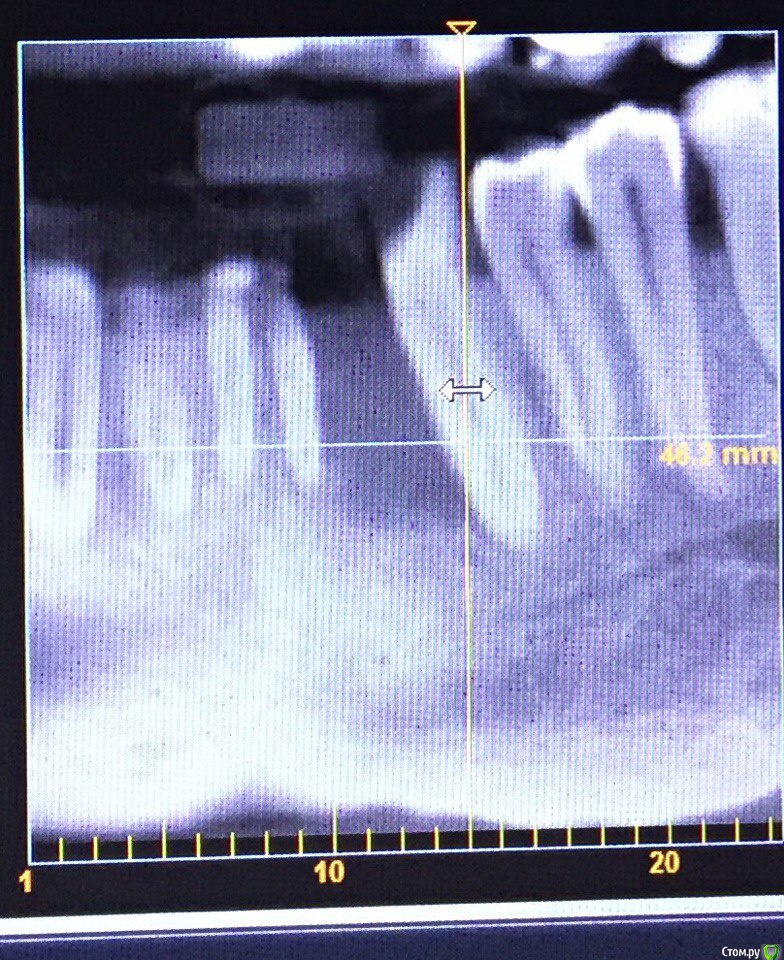

Evikrol Опубликовано 23 сентября, 2016 Поделиться Опубликовано 23 сентября, 2016 Тоже думаете удалить 33,31 и НКР? Ссылка на комментарий

АнтонТЛТ Опубликовано 24 сентября, 2016 Поделиться Опубликовано 24 сентября, 2016 что сдесь даст зондирование и прицельный?Дадут понять, как действительно обстоят дела с костными перегородками. На кт из-за толщины среза может быть не видна тонкая костная перегородка. 1 Ссылка на комментарий

Доктор Добрых Дел Опубликовано 24 сентября, 2016 Поделиться Опубликовано 24 сентября, 2016 Дадут понять, как действительно обстоят дела с костными перегородками. На кт из-за толщины среза может быть не видна тонкая костная перегородка.возможно.Но вот этот"карман" в апикальной части клыка, по-моему, говорит о том, что перегородки там нет. 1 Ссылка на комментарий

krokomot Опубликовано 25 сентября, 2016 Поделиться Опубликовано 25 сентября, 2016 возможно.Но вот этот"карман" в апикальной части клыка, по-моему, говорит о том, что перегородки там нет.карманы бывают разные одно-, двух- трехстеночные, тактика будет разная. Ссылка на комментарий

Доктор Добрых Дел Опубликовано 25 сентября, 2016 Поделиться Опубликовано 25 сентября, 2016 карманы бывают разные одно-, двух- трехстеночные, тактика будет разная.Бывают конечно, но речь не идёт о парадонтологии. Речи об отсутствии 32 и необходимости аугментации. Согласен данный снимок не отражает картину полностью, но будем реалистами - вероятность того, что там сохранены межкорневые перегородки стремится к нулю. 2 Ссылка на комментарий